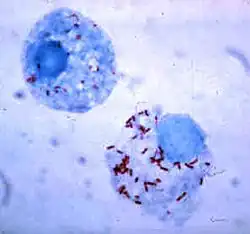

Monocytes develop in the bone marrow and reach maturity in the blood. Mature monocytes have large, smooth, lobed nuclei and abundant cytoplasm that contains granules. Monocytes ingest foreign or dangerous substances and present antigens to other cells of the immune system. Monocytes form two groups: a circulating group and a marginal group that remain in other tissues (approximately 70% are in the marginal group). Most monocytes leave the blood stream after 20–40 hours to travel to tissues and organs and in doing so transform into macrophages[69] or dendritic cells depending on the signals they receive.[70] There are about 500 million monocytes in one litre of human blood.[3]

This type of phagocyte does not have granules but contains many lysosomes. Macrophages are found throughout the body in almost all tissues and organs (e.g., microglial cells in the brain and alveolar macrophages in the lungs), where they silently lie in wait. A macrophage's location can determine its size and appearance. Macrophages cause inflammation through the production of interleukin-1, interleukin-6, and TNF-alpha.[73] Macrophages are usually only found in tissue and are rarely seen in blood circulation. The life-span of tissue macrophages has been estimated to range from four to fifteen days.[74]

Macrophages can be activated to perform functions that a resting monocyte cannot.[73] T helper cells (also known as effector T cells or Th cells), a sub-group of lymphocytes, are responsible for the activation of macrophages. Th1 cells activate macrophages by signaling with IFN-gamma and displaying the protein CD40 ligand.[75] Other signals include TNF-alpha and lipopolysaccharides from bacteria.[73] Th1 cells can recruit other phagocytes to the site of the infection in several ways. They secrete cytokines that act on the bone marrow to stimulate the production of monocytes and neutrophils, and they secrete some of the cytokines that are responsible for the migration of monocytes and neutrophils out of the bloodstream.[76] Th1 cells come from the differentiation of CD4+ T cells once they have responded to antigen in the secondary lymphoid tissues.[73] Activated macrophages play a potent role in tumor destruction by producing TNF-alpha, IFN-gamma, nitric oxide, reactive oxygen compounds, cationic proteins, and hydrolytic enzymes.[73]